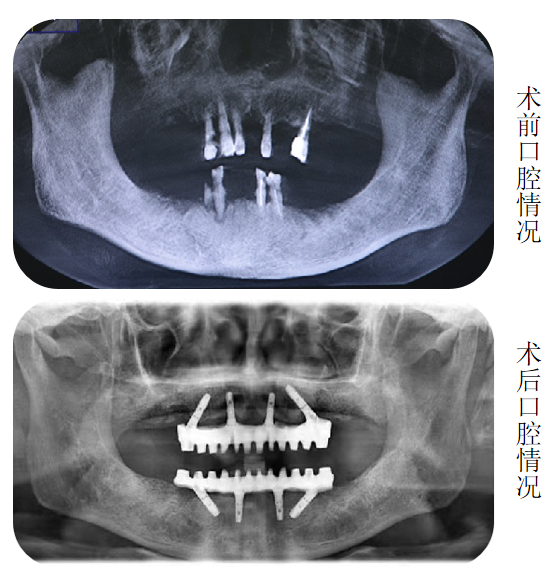

“这个您不用担心。”海涛口腔种植科唐主任经过口内数据分析和会诊后告诉李大妈:“我们借助计算机,设计出您口腔内8个适合种植的位置,利用海涛“一天得”全口种植牙技术,上下半口各4颗种植体就能分别完成半口牙修复,恢复全口咀嚼功能。”

上午进入手术室时还是无牙状态的李大妈,下午出来时已戴上固定义齿,激动地说:“海涛口腔的技术真是了不起,我这多年的缺牙问题终于解决了。”

更少的种植体+无需植骨+精准的力学设计,当天种出一口新牙

海涛口腔唐主任介绍,海涛“一天得”全口种植牙是海涛口腔的特色技术,数字化导航定位,植入精准,只需植入4颗或6颗种植体就可以解决半口无牙问题,并且当天种牙,当天就可戴牙吃饭。整个手术过程一次性完成,大大缩短了患者的就诊时间和次数,节省了治疗费用,价格相比传统种植牙省了很多。同时,该技术采用2毫米的钛丝,结合国际先进的口内冷焊接技术焊接而成,稳定性非常好。与此同时,该技术打破传统种植技术瓶颈,破解牙槽骨萎缩、骨量不足等种植难题,无需植骨不增加额外费用,让这一缺牙群体也能实现种植牙。